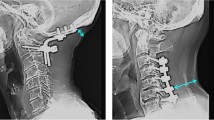

We report three cases of oesophageal complications due to pressure necrosis secondary to screws post anterior plate fixation of the cervical spine. Two of the patients were treated using primary closure; and the third by conservative treatment, which consisted of wound drainage and an external orthotic device application. We recommend the early surgical closure and removal of the metallic implant with debridement as the first option of treatment. In the event that this option is not suitable, we suggest that wound drainage, tube feeding and parenteral antibiotics may be an appropriate alternative.

Hanci, M., Toprak, M., Sanoğlu, A. et al. Oesophageal perforation subsequent to anterior cervical spine screw/plate fixation. Spinal Cord 33, 606–609 (1995). https://doi.org/10.1038/sc.1995.128